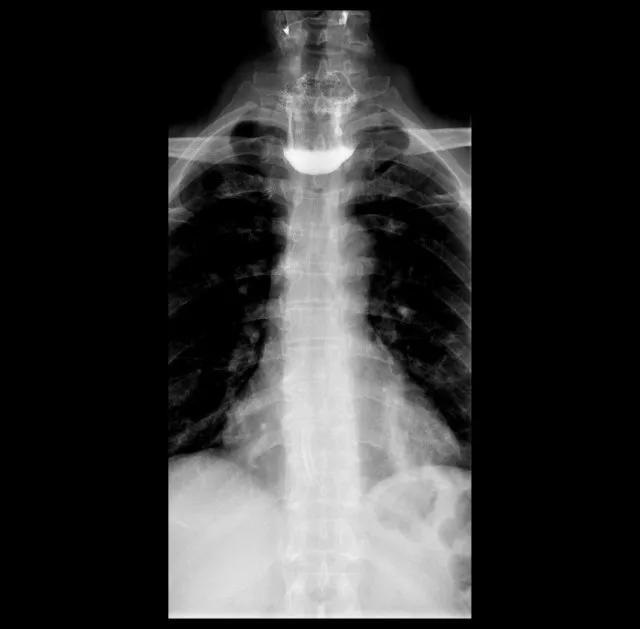

▲术前上消化道造影可见食管上段巨大囊袋影